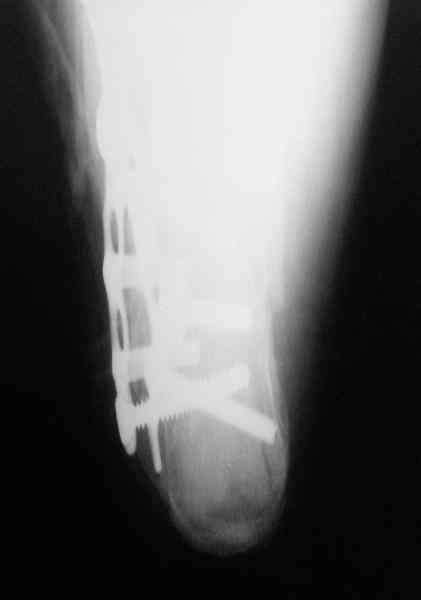

Пяточной пластиной

Its a comminuted one.

I myself would reduce it with EX-FIX and depending on the result would consider a plate on the table.

MOST OF MY COLLEGUES WOULD OPEN IT LATERALLY( a flap) and having a proper reduction would put a plate.

Сустав похоже интактен, киста под вопросом,даже при наличии опыта остесинтеза пластиной, в данном случае выведение правильного угла и фиксация спицами более чем достаточно, да и намного спокойнее сон у хируга.

Перелом безусловно внутрисуставной. Киста-не киста принципиального значения не имеет.